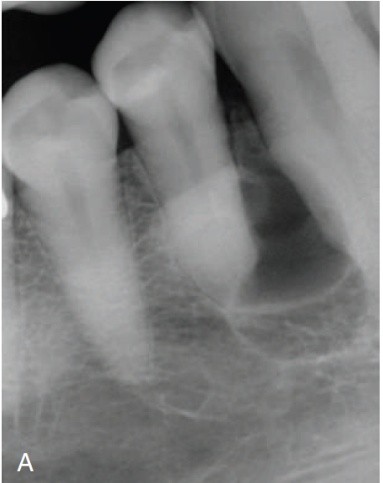

1. (Select ONE OR MORE correct answers)

The radiograph shows evidence of